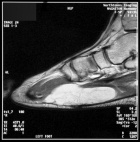

N.H. - 15 year old white male with a slowly growing mass over the plantar aspect of his left foot

Zoom image: Radiological image Radiological image.